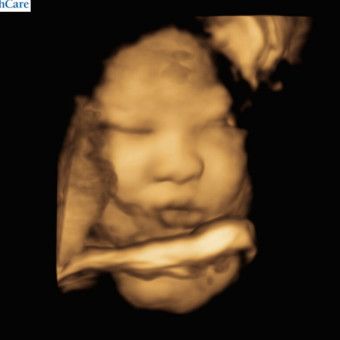

Baby Ghimire

Baby ghimire & Rupesh Ghimire